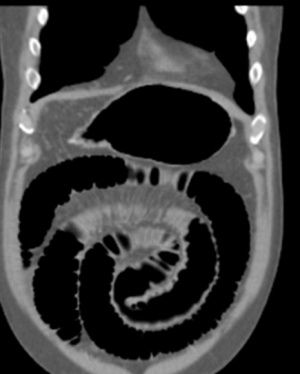

- ב- CT אפשר לראות תמונה של חסימת מעי דק עם הרחבה של לולאות מעיים ואת האבן החוסמת (תצלום 44.8)

| תצלום 44.8: חסימת מעי מאבן מרה (חץ מסמן את האבן החוסמת). | |